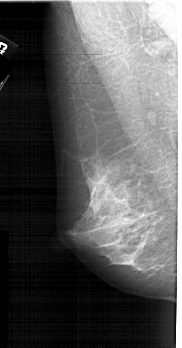

A_1907_1.RIGHT_MLO

RIGHT_MLO LINES 5101 PIXELS_PER_LINE 2566 BITS_PER_PIXEL 12 RESOLUTION 43.5 OVERLAY

FILE: A_1907_1.RIGHT_MLO.OVERLAY

TOTAL_ABNORMALITIES 1

ABNORMALITY 1

LESION_TYPE CALCIFICATION TYPE PLEOMORPHIC DISTRIBUTION CLUSTERED

ASSESSMENT 4

SUBTLETY 2

PATHOLOGY MALIGNANT